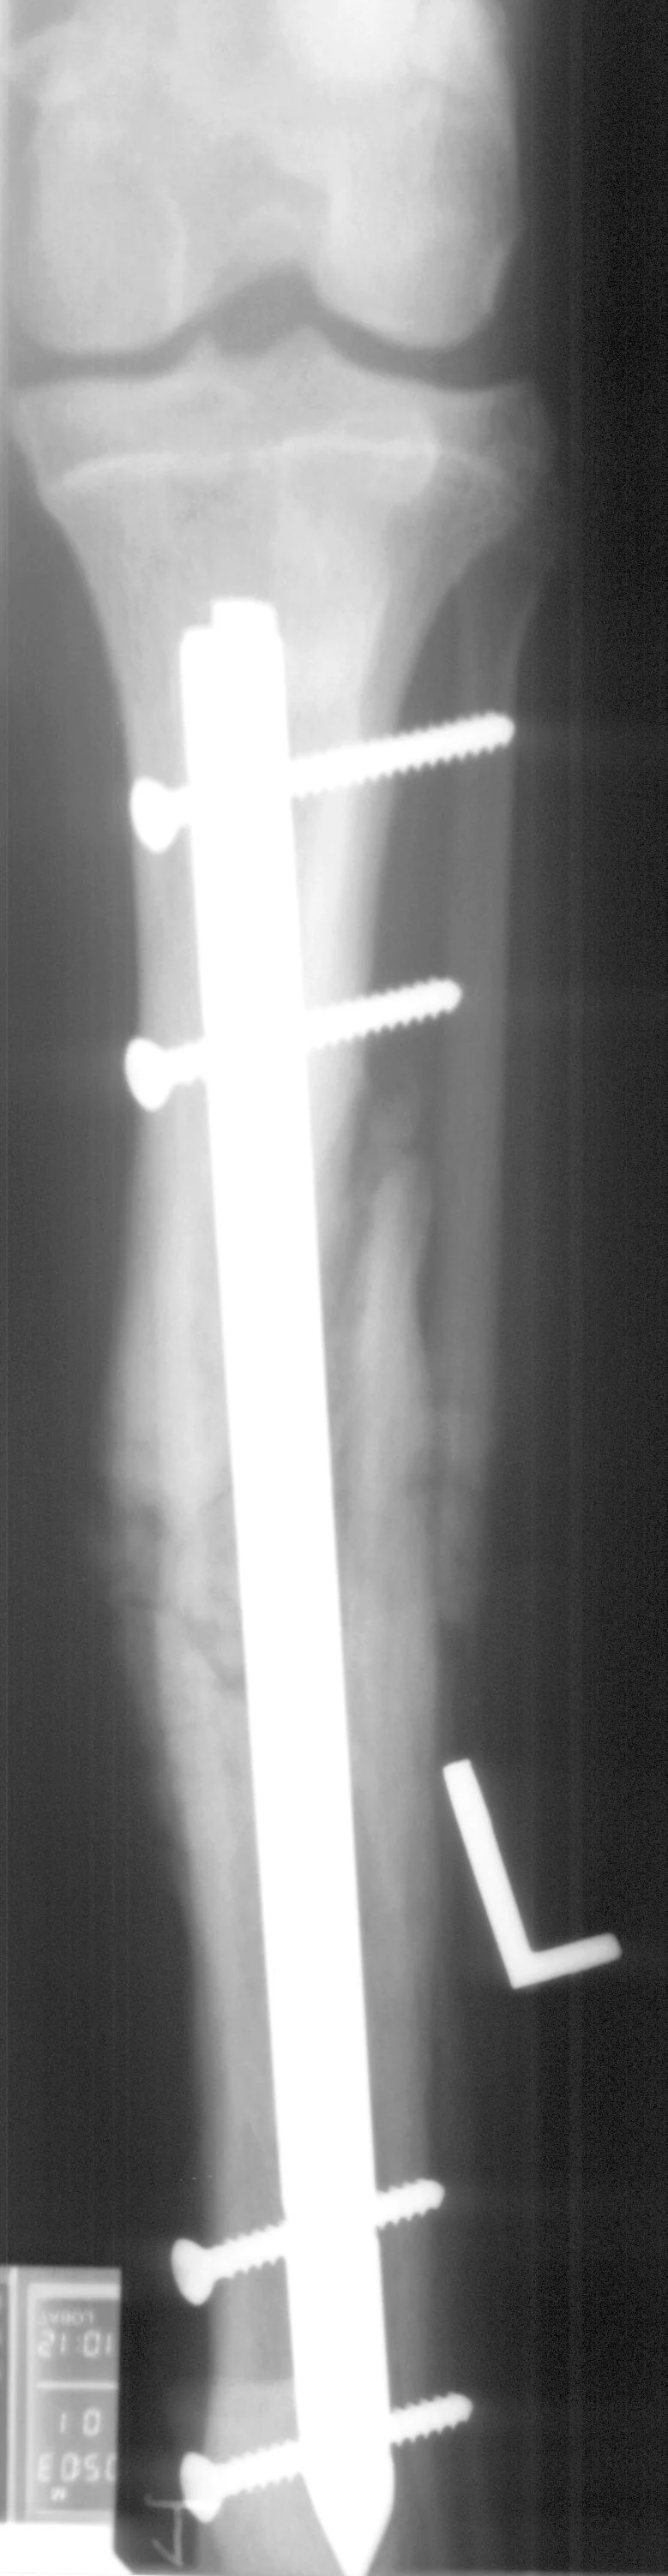

The interlocking-nail system (Innovative Animal Products, Rochester, MN) is another effective implant system for biologic management of comminuted fractures in dogs and cats.1 The interlocking nail is a modified Steinmann pin having transverse holes designed to accommodate screws or bolts. The addition of screws or bolts increases the ability of the pin to resist rotational and compressive forces at the fracture site (Figures 2A, B). This type of fixation is commonly used for stabilization of fractures of the femur and tibia in humans.

Interlocking nails are used in dogs and cats for repair of fractures of the humerus, femur, and tibia. The interlocking-nail system is less expensive than a bone-plate system but has similar biomechanical properties.8 Interlocking nails are easy to apply and are a good option for general practitioners who do not want to invest in a bone-plate system.

Fractures managed using interlocking nails and biologic technique develop extensive bridging callus and early return to function. A minimally invasive surgical approach (note the surgical skin staples) was made to this fracture to minimize disruption of the blood supply to the bone fragment. The fracture fragments quickly become incorporated in the callus if soft tissue attachments can be maintained.